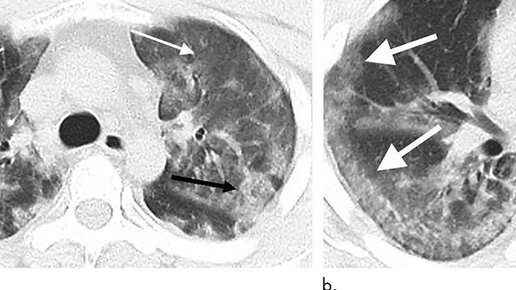

В специальном докладе врачей из КНР и США перечислены особые признаки, на которые должны обращать внимание радиологи, чтобы отличить на изображениях компьютерного томографа (КТ) коронавирус (вирус 2019-ncov) от банальной пневмонии...